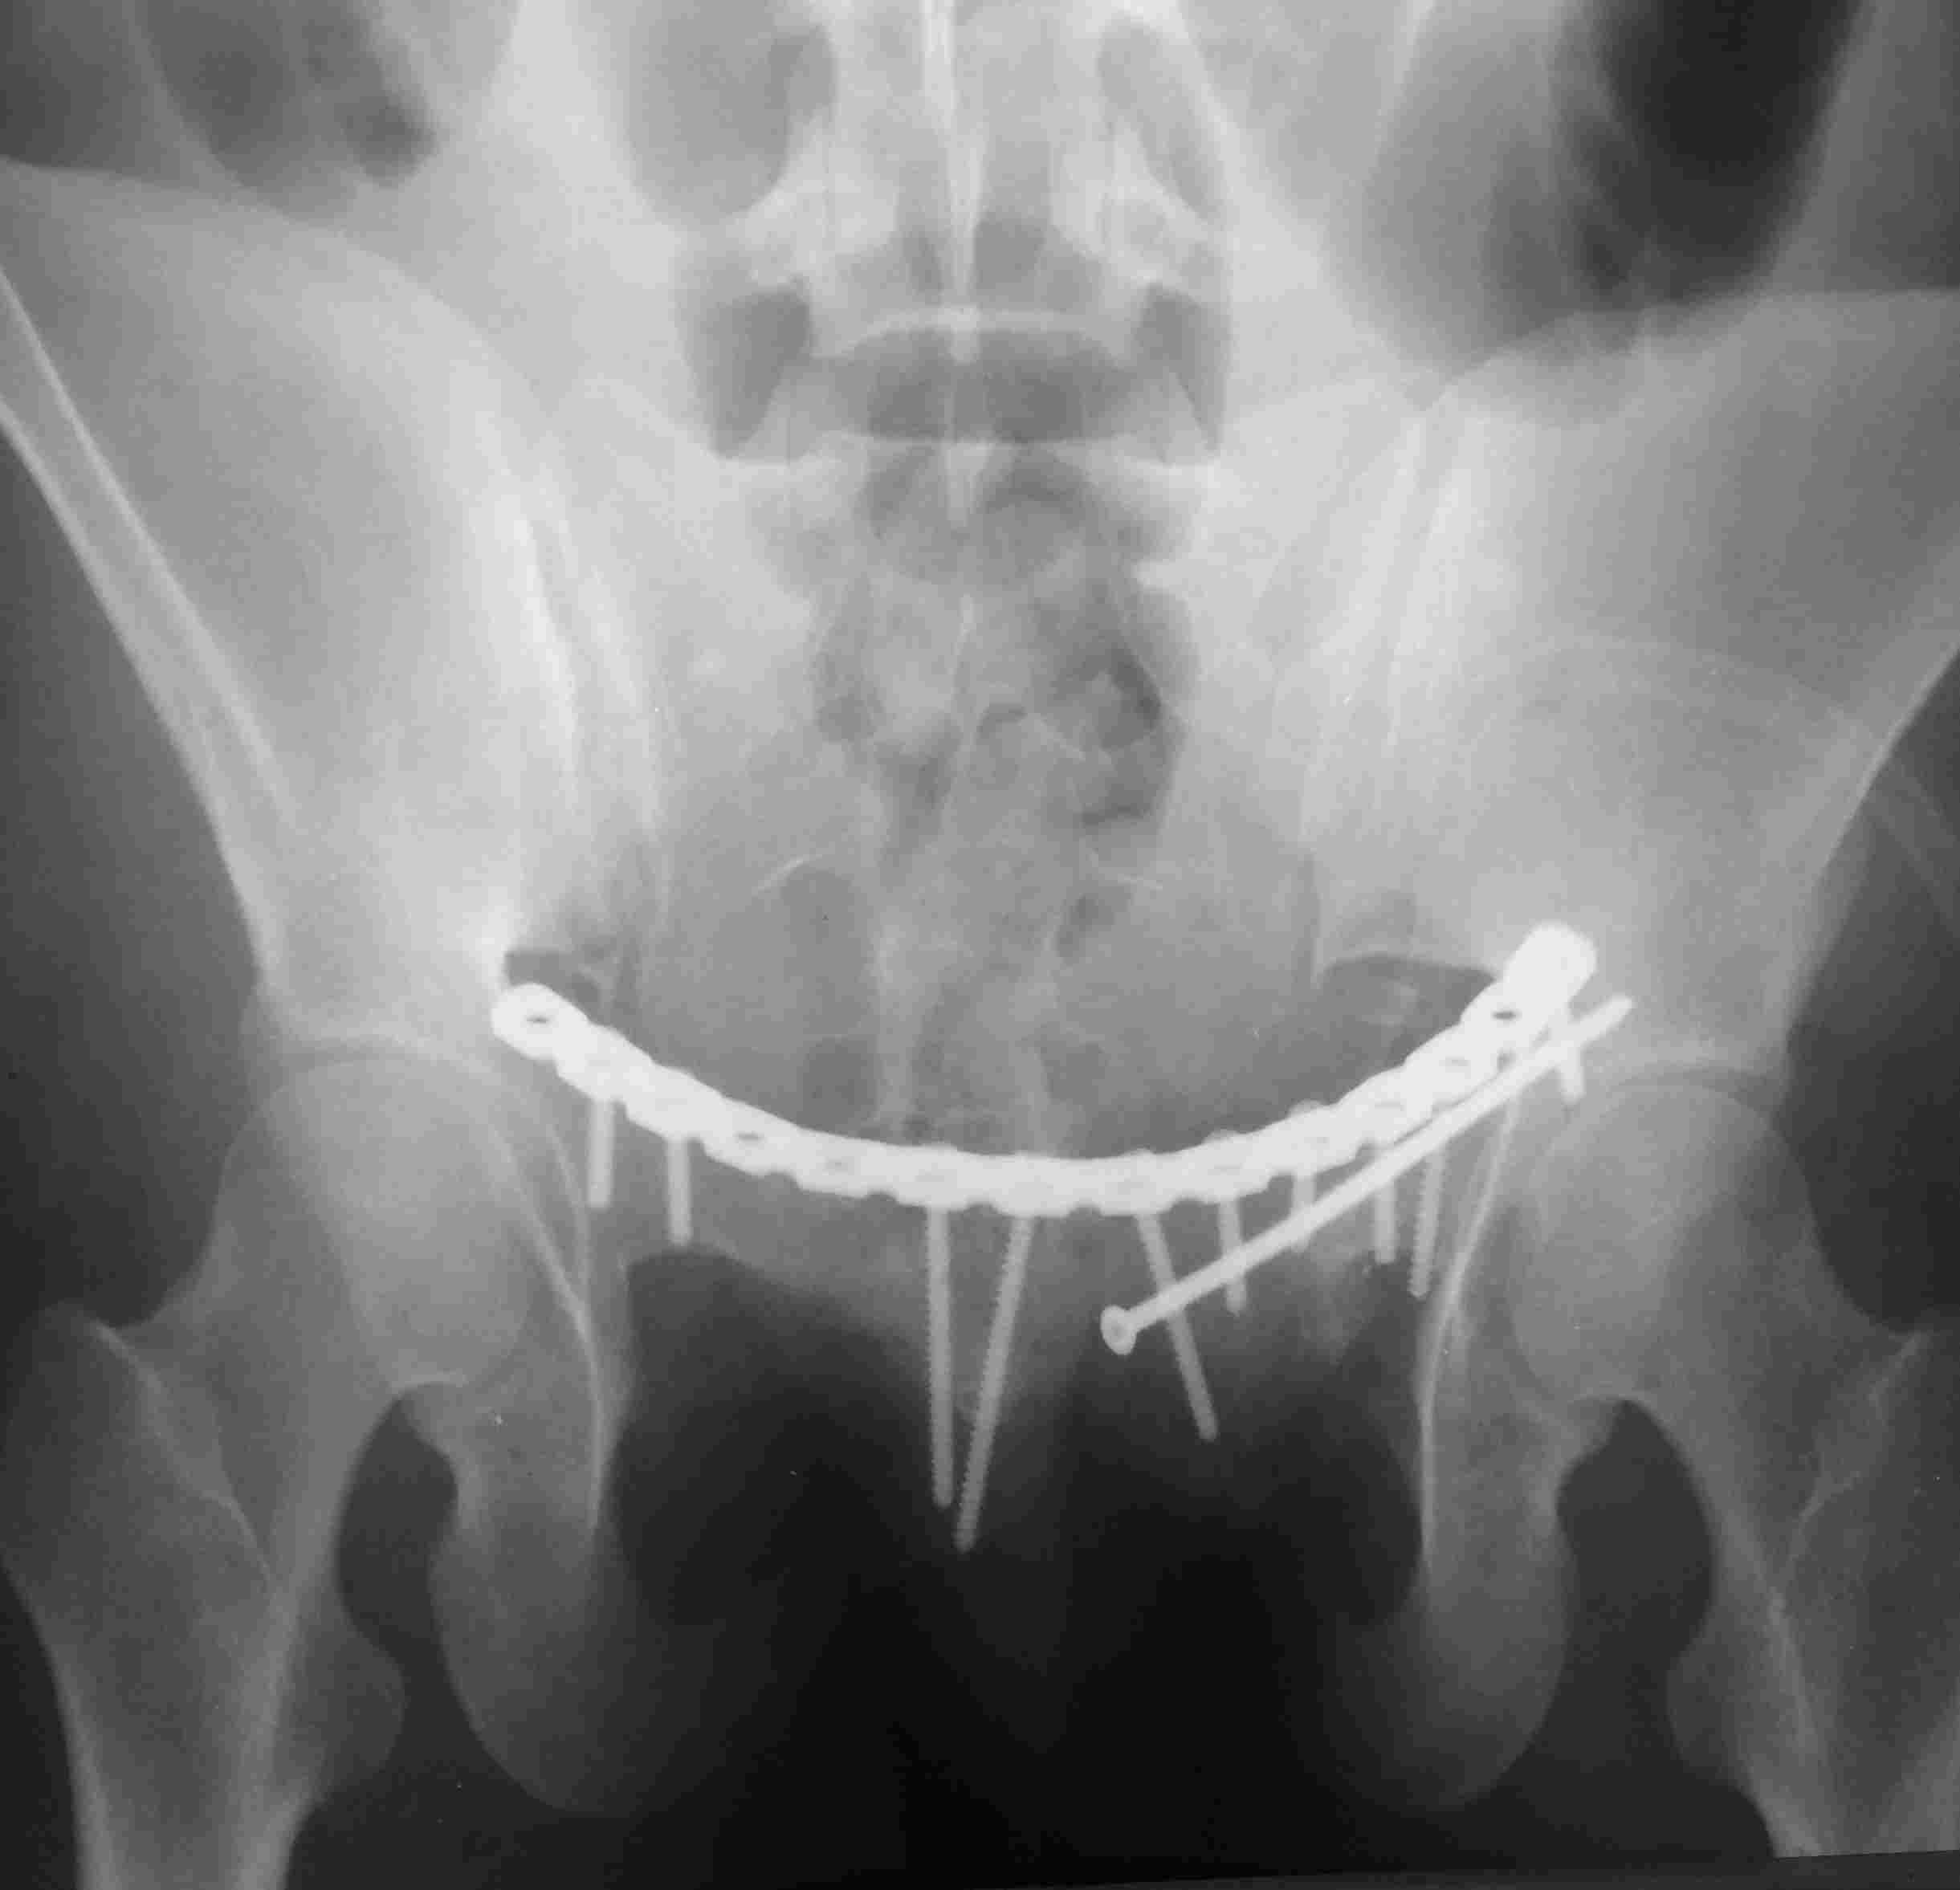

[Ortho] повреждение таза с необычным смещением

Постоп. Верхняя ветвь возле шейки мочевого пузыря, нижняя так же где-то

глубоко в мышцах, ротирована. Обе практически лишены кровоснабжения.

лонное сочленение фактически свободно лежащее, справа  почти целое, но

ветви сломаны возле него. Слева часть лонного сочленения цела на 2/3.

интраоперационно подвижность правой половины таза. Постоп все стабильно,

но все же планирую дополнительно провести IS винт справа.